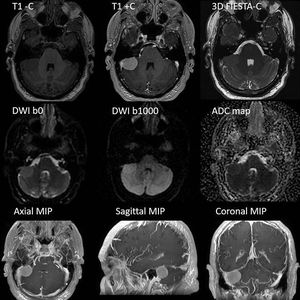

High resolution meningioma MR Imaging, based on anatomical and functional acquisitions. DWI PROPELLER makes feasible the DW Imaging of inhomogeneous areas, such as IAC, without distortions. Thin MIP of the volumetric T1 acquisition can be used for the (time-effective) evaluation of vessels proximity. Images courtesy of Christos Tsiotsios